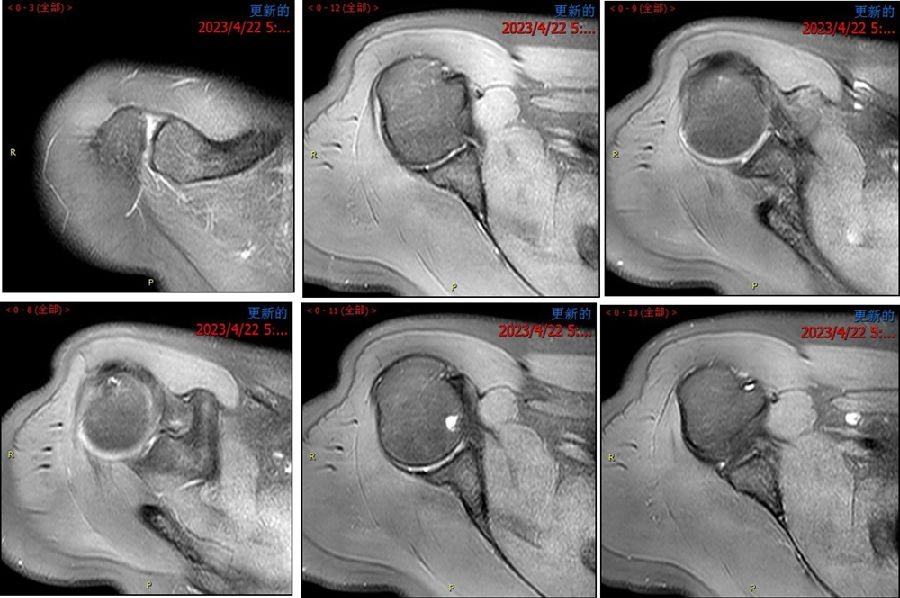

典型病例,苏X,男,36岁。主诉左肩关节反复脱位2年。诊断左肩复发性脱位、左肩胛盂骨折(骨性Bankart损伤)、左肱骨头Hill-Sachs损伤。

手术方案:左肩关节镜下探查清理、Latarjet术。

图42-43、视频17 术前查体,ASES评分57分,ISIS评分4分,Beighton评分2/9分

图44 术前MRI

视频18

图45 CT D=26mm d=8mm(上患侧,下健侧)

图46 CT d/D=30.7% GT=0.83D-d=13.6mm Hill-Sachs损伤I级,骨缺损 >25%